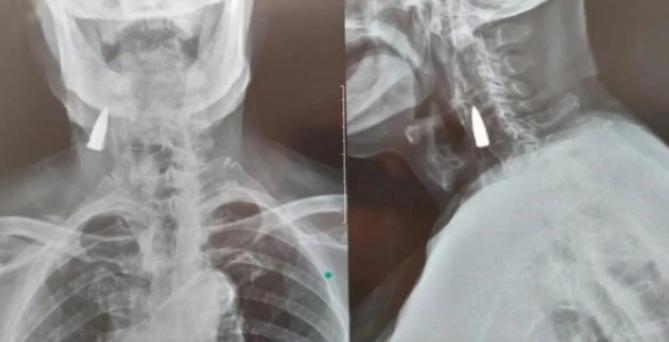

10月21日

山東臨沂一位95歲老人摔倒后

拍X光發(fā)現(xiàn)頸部

有一顆戰(zhàn)爭時期留下的子彈